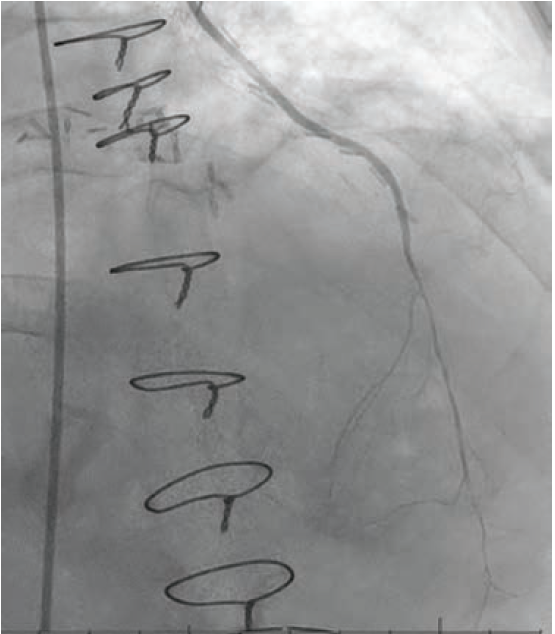

Imaging. Cardiac catheterization showed mild pulmonary hypertension, oxygen step up in right ventricle (RV) with Qp:Qs 2.8:1, severe native CAD, patent LIMA to LAD and RIMA to OM3. There was severe diffuse disease (90-95%) in the native LAD after the LIMA anastomosis (Figure 2, Video 2 [at end of case section]), which was the culprit behind the recent MI. Transesophageal echocardiogram (TEE) confirmed a large, antero-apical aneurysm and postinfarct VSD that measured up to 14 mm (Video 1 [at end of case section]). During multidisciplinary heart team discussion, he was deemed high risk for redo open heart surgery (LV aneurysmectomy and patch VSD closure) and was referred for percutaneous VSD closure.

Diagnostic cardiac catheterization with native coronary angiography as well as bypass graft angiography revealing severe, diffuse disease in the LAD distal to LIMA anastomoses.

LAD = left anterior descending artery; LIMA = left internal mammary artery